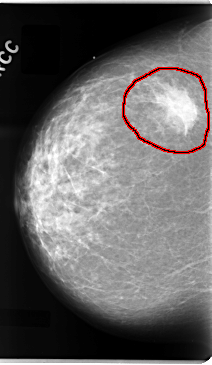

C_0094_1.RIGHT_CC

FILE: C_0094_1.RIGHT_CC.OVERLAY

TOTAL_ABNORMALITIES 1

ABNORMALITY 1

LESION_TYPE MASS SHAPE IRREGULAR MARGINS ILL_DEFINED

ASSESSMENT 5

SUBTLETY 5

PATHOLOGY MALIGNANT

TOTAL_OUTLINES 1

BOUNDARY